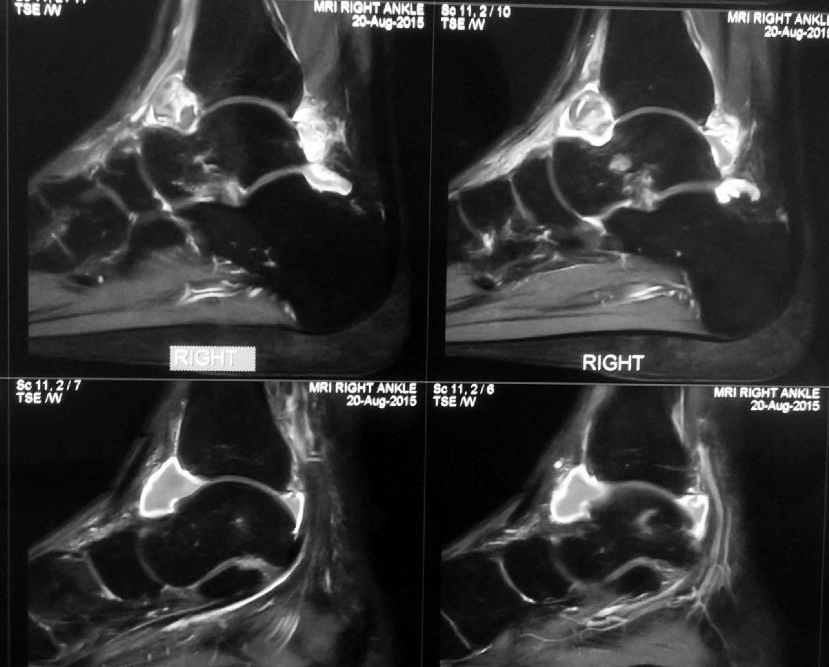

An MRI scan of his right ankle was done and it showed an intra-articular nodule / tumour over the front of his right ankle. It was consistent with a pigmented villonodular synovitis (PVNS).

This tumour has been growing in his right ankle for a long time. It was dormant and asymptomatic until one fine day when he caught part of the tumour between the surfaces of the joint. This caused bleeding and occasional “infarction” of the tumour. This leads to the acute onset of pain and swelling as in this case.